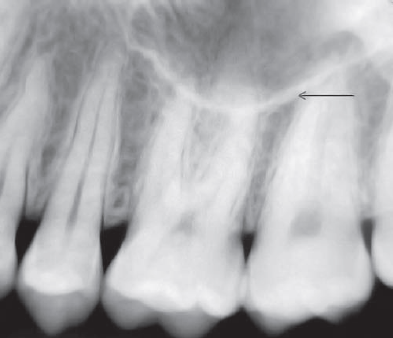

63. What arrow shows?

Nasolabial Fold An oblique line demarcating a region that appears to be covered by a veil of slight radiopacity frequently traverses periapical radiographs of the premolar region. The line of contrast is sharp, and the area of increased radiopacity is posterior to the line.